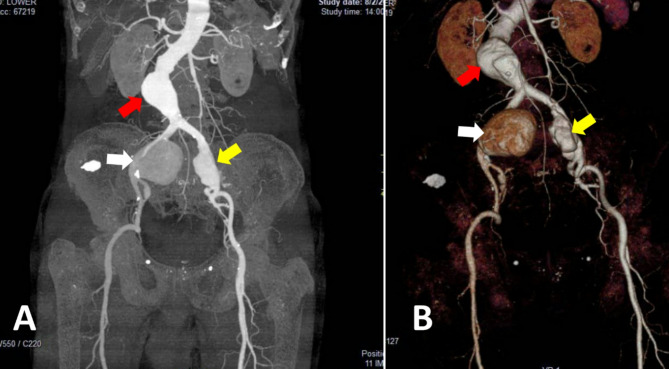

Case presentation: This case reports a 72-year-old male complaining of pain in the right iliac fossa and hypogastric region, radiating to the back. An abdominal ultrasound revealed a right dissected common iliac aneurysm, left common iliac aneurysm and an abdominal aortic aneurysm. Further investigation confirmed the same findings. Several hours later, the decision of emergency surgery was done due to signs of hemorrhagic shock caused by ruptured unilateral iliac aneurysm. The aneurysms were successfully repaired by aorto-bi-iliac dacron-graft bypass and palpable femoral pulses noted at the end of the surgery.